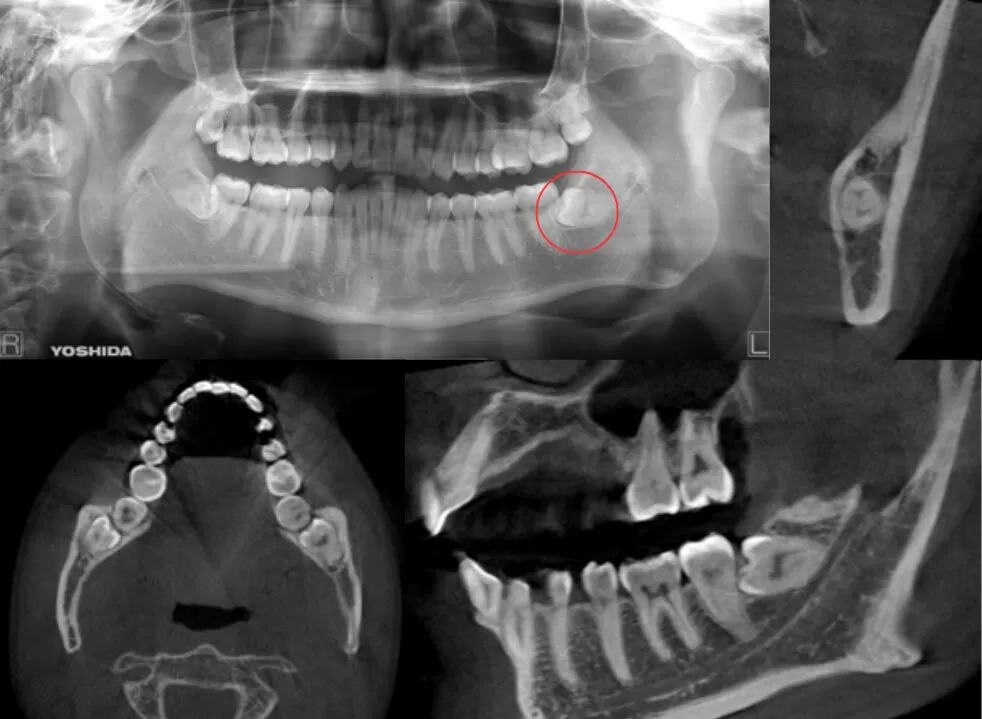

歯冠が一部露出、一部被覆している症例

| 患者情報 | 26歳 男性 |

| 手術時間 | 25分 |

| 治療内容 | 親知らず抜歯 |

| グレゴリー分類 | クラスⅡ position B |